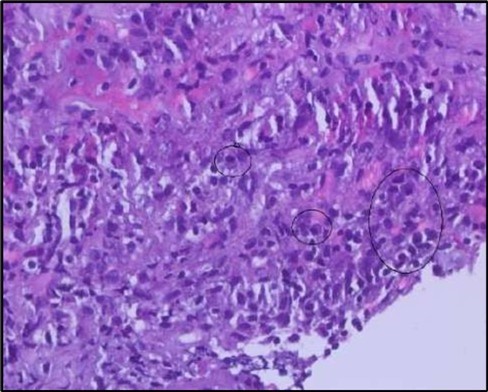

Figure 5a.OS, Hematoxylin and eosin (H&E) stained section of the corneal specimen demonstrating full-thickness epithelial loss with underlying stromal necrosis.

Figure 5b.OS, High-power H&E view showing dense inflammatory infiltration within the corneal stroma composed predominantly of lymphocytes and numerous plasma cells (circles highlight plasma cells).

Histopathological examination revealed a dense infiltration of CD138-positive plasma cells within the excised conjunctival tissue (Figure 5b, Figure 5c, Figure 5d). This finding supports an antibody-mediated immunopathogenesis in Mooren’s ulcer, consistent with Type II and Type III hypersensitivity mechanisms described in the literature 20, 21. The prominent presence of CD138- positive plasma cells provide a clear pathological rationale for conjunctival resection, as excision of the immunologically active perilimbal conjunctiva effectively removes the local 'factory' of autoantibodies that drive corneal stromal destruction, thereby halting ongoing tissue damage 21.